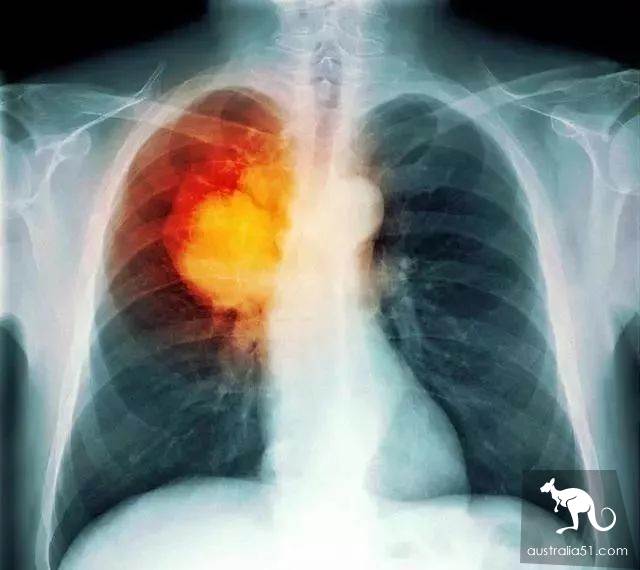

Lung cancer has become the highest incidence of cancer in China.

It is also the cancer with the highest death rate.

Nurse Amanda Eller, from North Carolina, shared a video on fb with ordinary people's lungs on the right, pink, healthy and flexible when inflated.

On the left is the lungs of smokers, the surface is black, lack of elasticity.

Now people physical examination, X-rays and CT are afraid of radiation, in fact, these radiation is very strong, but can not compare to a place, that is, smokers' lungs!

This is the strongest place in the world.

Polonium and lead in cigarettes emit ionizing radiation all the time.